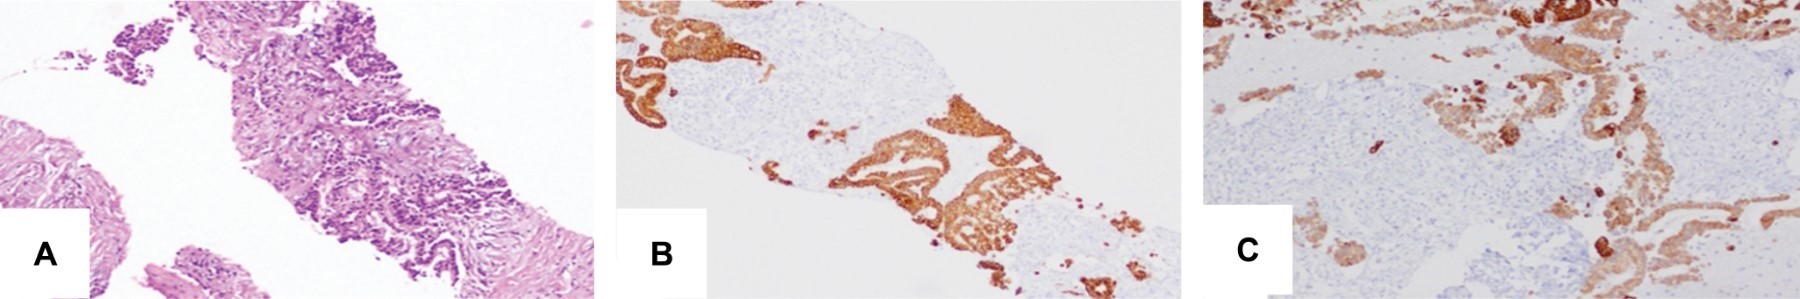

Cholangiocarcinoma is a neoplasm of the bile duct epithelium. Its frequency of appearance is low despite being the second most common primary liver cancer in the world (incidence 2%). Predominates in men have a poor prognosis and high mortality; survival in early stages is 40 months with surgery and 12 with advanced-stage chemotherapy. The low symptoms specificity at the presentation and local tumor infiltration at the time of diagnosis usually prevent the possibility of radical surgical resection. Suspicion of cholangiocarcinoma is based on signs of biliary obstruction and elevation of tumor markers (Ca 19-9). We will refer to a patient with cholangiocarcinoma of the hilar confluence (Klatskin tumor) and the magnetic resonance findings.

Figure 1